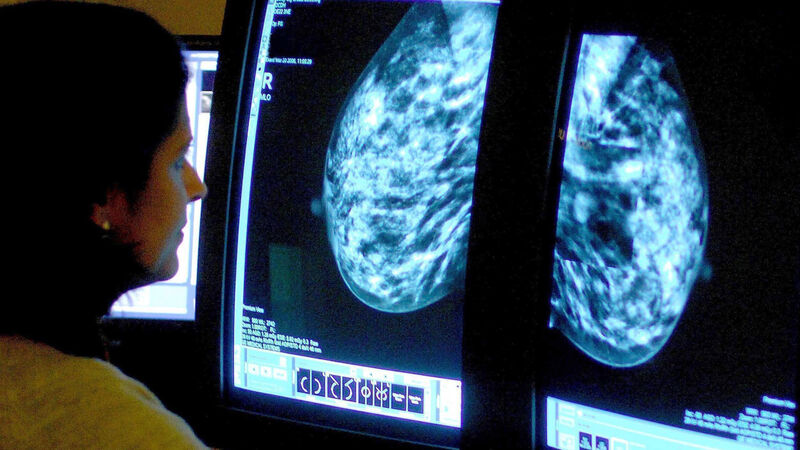

Signs of heart disease can be picked up in breast cancer screenings through the use of artificial intelligence (AI), researchers have found.

Experts used AI to look for calcification in breast arteries - a substance that increases the risk of heart attack, stroke and early death.

AI was used to look for calcium deposits in the arteries of breast tissue, which is known to harden arteries and can increase the risk of heart attack and stroke.